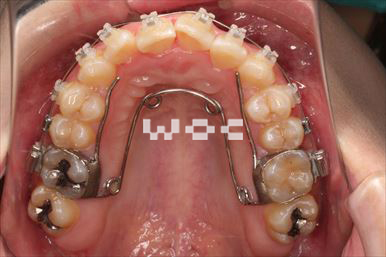

治療中2

治療中3

治療中4

出っ歯舌側矯正

上下舌側矯正を希望。

通院状況や歯みがきの協力が良かったため、1年7ヶ月で治療を終えることができました。※装置と注意事項に関しては、大人の矯正装置一覧へ。

- 年齢:20歳女性

- 主訴:出っ歯が気になる

- 基本矯正料金:120万円

- 治療期間:1年7ヶ月

- 抜歯部位:上顎両側第一小臼歯